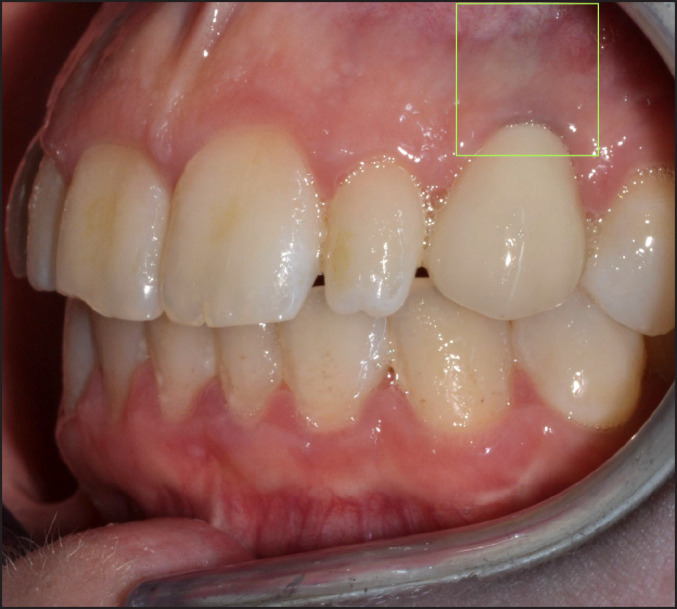

Material and methods: Ten patients with a single implant supported prosthesis connected to zirconia or titanium abutments were invited at the five-year control. A clinical examination and a survey on experience of function and appearance were conducted. A mucosa biopsy taken in close vicinity to the implant were analysed by real-time polymerase chain reaction (qPCR) and presence of particles in a scanning electron microscope/energy-dispersive X-ray spectroscope (SEM/EDX). Cytological smear samples were collected and analysed through inductively coupled plasma mass spectrometry (ICP-MS) to investigate presence of particles on implant heads.

Results: In total, 9 patients participated in the study, five with titanium abutments and four with zirconia abutments. All patients were satisfied with function and aesthetics. Titanium and iron particles were detected in mucosa biopsies. The ICP - MS analysis demonstrated presence of zirconia and titanium. Several proinflammatory genes were upregulated in the zirconia abutment group.